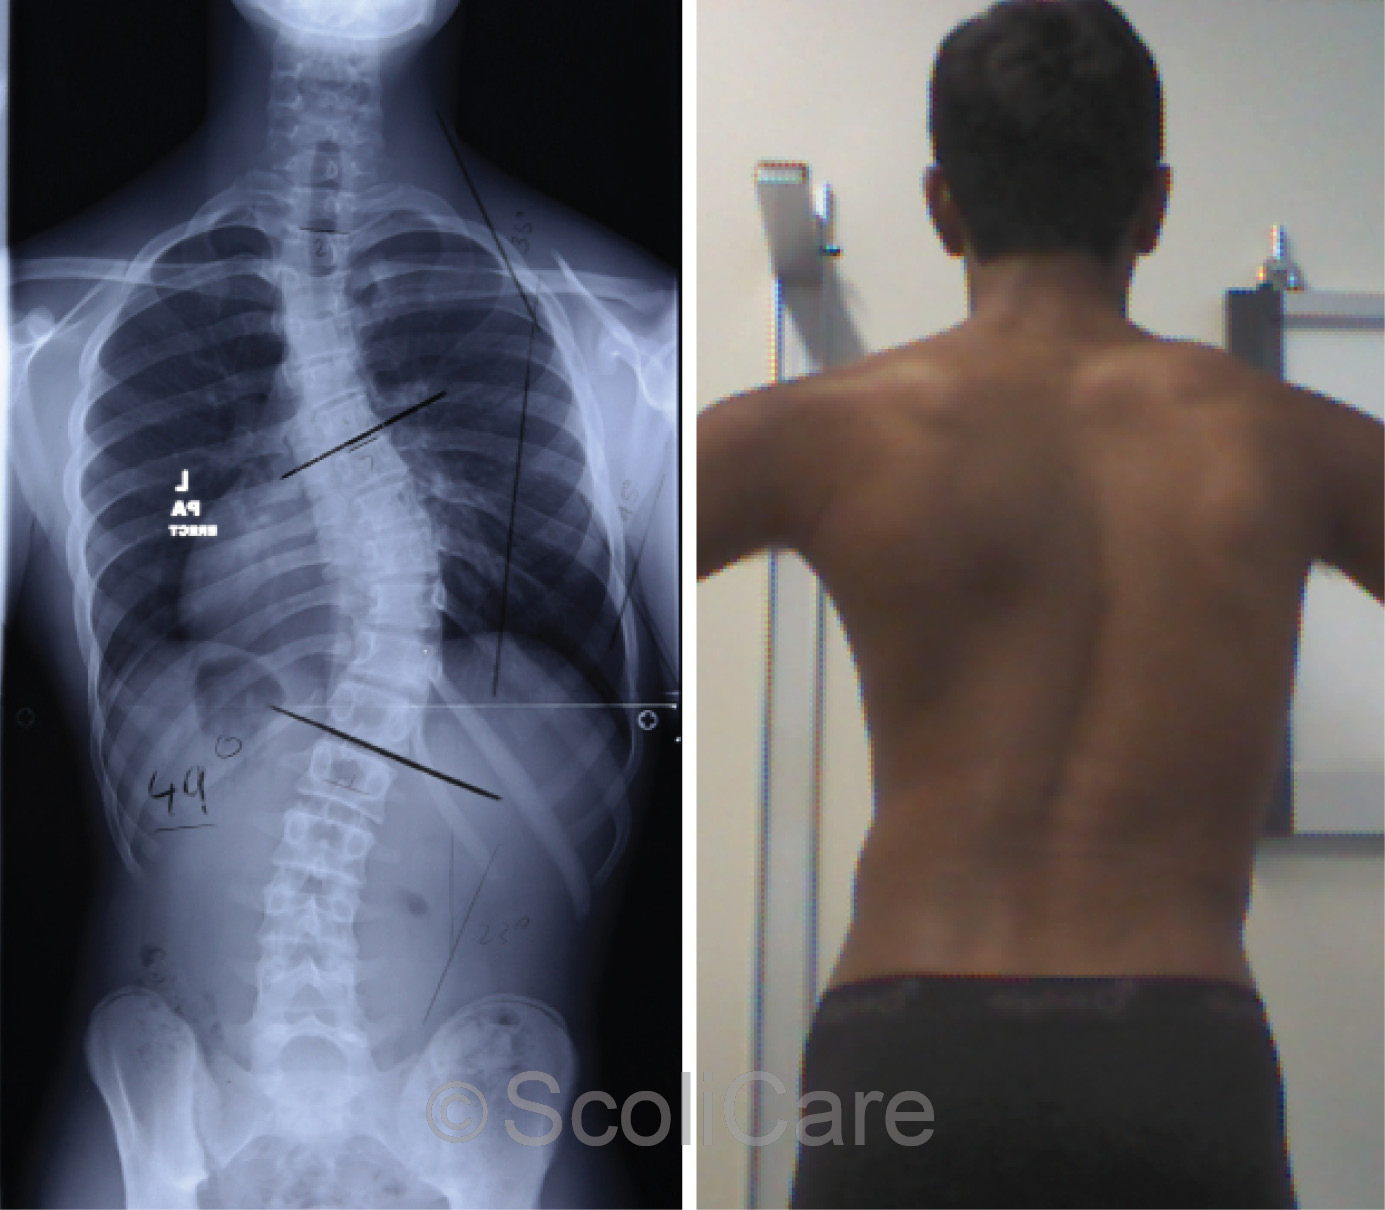

Male patient aged 14 years with a right thoracic curve measured at 49 degrees.

The patient presented to the ScoliCare Clinic one year later for brace therapy. The patient had continued with his sporting and athletic pursuits. Plain films taken at the time of this consultation revealed the patient was Risser 3 and the scoliosis had progressed a further 10°, measuring 49° (Figure 1).

Figure 1: Standing posteroanterior x-ray demonstrating a 49° right thoracic scoliosis (Left),

Standing posteroanterior postural photograph (Right).